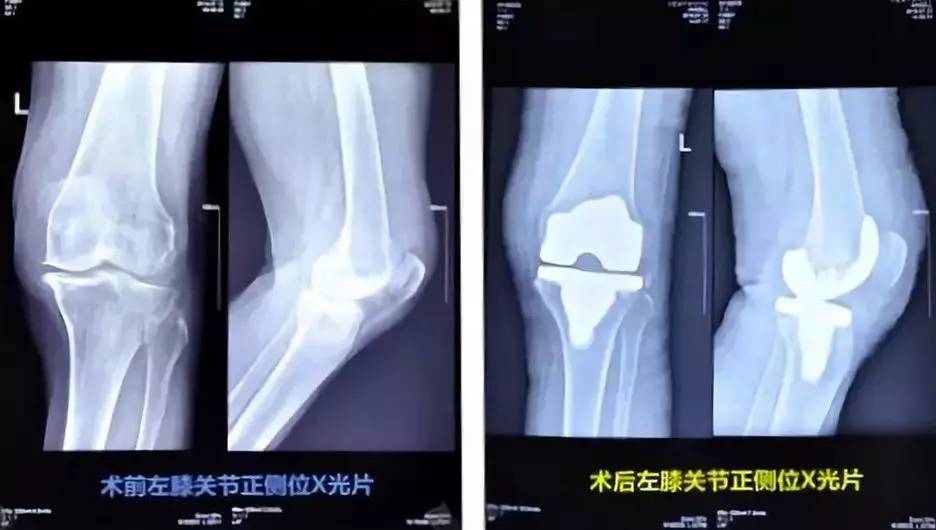

合肥肥东县86岁高龄的李老太,左腿膝关节疼痛的毛病伴随了她多年,以前上下楼梯时就痛得厉害,膝关节反复肿胀,饱受病痛折磨。此前她曾辗转多家医院进行保守治疗,均不见好转。

今年7月,李老太来到康华医院骨外科就诊,专家诊断她的左侧膝关节退行性病变,关节间隙狭窄,软骨下硬化明显,左膝关节骨性病变严重。医院骨外科团队成功地为她实施了人工全膝关节置换术,术后第三天,她就下床开始按医生治疗方案进行康复训练,在医护人员的搀扶下训练行走。目前李老太已康复。